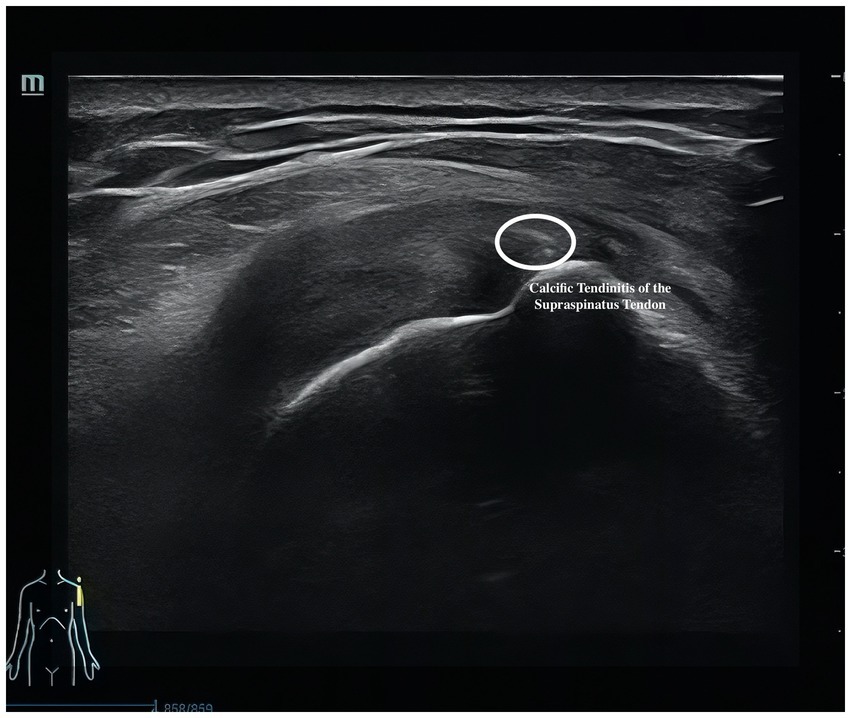

Musculoskeletal ultrasound is a practical and noninvasive method for detecting structural abnormalities commonly associated with PSSP. Key indicators include the distance from the acromion to the greater tuberosity of the humerus (Figure 9), effusion around the long head of the biceps tendon sheath (Figure 10), calcification in the supraspinatus (Figure 11) and subscapularis tendons, and increased thickness of the subdeltoid bursa (Figure 12). Effusion around the biceps tendon sheath often reflects inflammation or tendinopathy, which can contribute to pain and limited mobility. Calcifications in the supraspinatus and subscapularis tendons are typically associated with chronic rotator cuff conditions that result in impingement and reduced range of motion. Thickening of the subdeltoid bursa is suggestive of bursitis, a frequent source of discomfort in PSSP patients (21).

Figure 11

Ultrasound image of a shoulder showing calcific tendonitis of the supraspinatus tendon. The affected area is circled, indicating the calcification deposit within the tendon structure.

Figure 11. Calcifications in the supraspinatus.